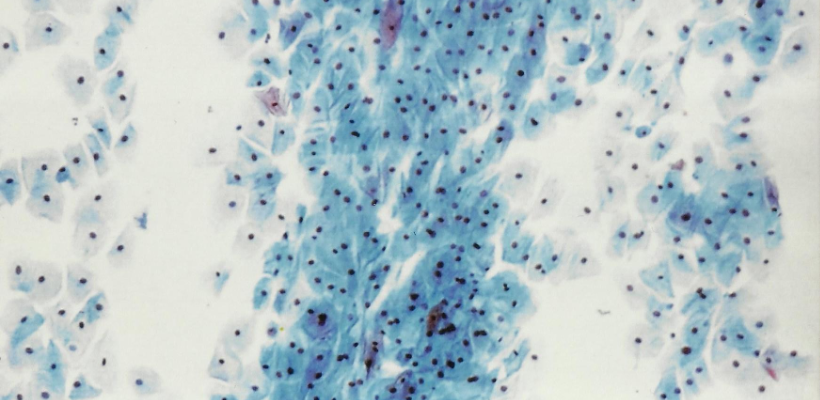

39 personnes dont 33 brûlés et 6 porteurs de plaies chroniques ont été traitées entre Février et Septembre 2012. Un à quatre centimètres carrés de greffe mince de peau saine autologue a été transformée par biodégradation des liaisons peptidiques, dans le but d'avoir un soluté riche en moyenne de 1,5 millions de cellules cutanées/cm². Cent minutes ont suffi. Une partie de ce soluté a été pulvérisée immédiatement sur les zones à traiter et le reste a été conservé par petites quantités dans des cryotubes à l’intérieur d’un container d’azote liquide. D’autres pulvérisations successives ont été effectuées lors de chaque pansement.

Technique originale repetitive sans culture in vitro préalable ayant apporté des cellules autologue: épidermiques, jonctionnelles et souches nécessaires à la reconstruction cutanée. Ses contre indications étant les plaies infectées, suintantes, hémorragiques et

granulomateuses.